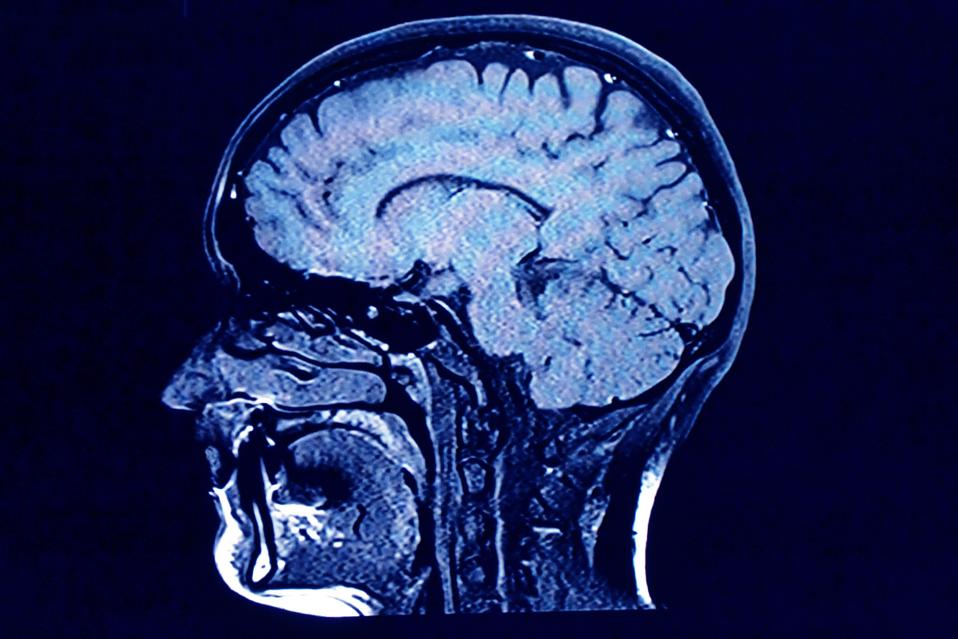

Mikroplastik Menumpuk dalam Otak Manusia: Ancaman Baru yang Mengkhawatirkan

Produksi plastik yang terus meningkat menyebabkan partikel-partikel kecil bernama mikroplastik terkumpul di mana-mana, termasuk di dalam tubuh manusia. Penelitian dari Universitas New Mexico menunjukkan bahwa mikroplastik lebih banyak ditemukan di otak dibandingkan dengan organ lainnya, seperti ginjal dan hati. Dalam sampel otak manusia, ditemukan 12 jenis polimer yang berbeda, dan rata-rata otak bisa mengandung sekitar 4.800 mikrogram mikroplastik per gram. Jumlah mikroplastik di otak juga meningkat pesat dalam delapan tahun terakhir.

Para ilmuwan menduga mikroplastik masuk ke dalam tubuh kita melalui makanan, terutama daging, yang terkontaminasi oleh plastik. Meskipun mereka belum tahu apakah mikroplastik berbahaya bagi kesehatan, mereka menemukan bahwa otak penderita demensia memiliki lebih banyak mikroplastik. Penelitian lebih lanjut diperlukan untuk memahami dampak mikroplastik pada kesehatan manusia, tetapi para peneliti berharap temuan ini dapat meningkatkan kesadaran masyarakat tentang keberadaan plastik di dalam otak mereka.